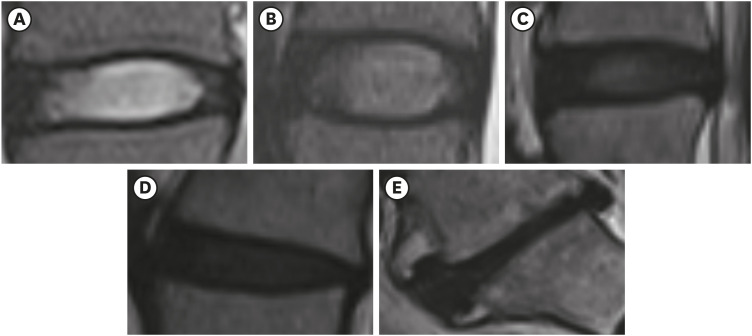

Fig. 2 shows the mean Pfirrmann grade and prevalence of grade 5 at each lumbar intervertebral disc level by age. The mean Pfirrmann grade was highest at L4/5 and showed an overall increase with age (p < 0.05 by one-way ANOVA), except for L4/5 and L5/S1 between 50–59 and 60–69 years of age. Grade 5 prevalence was higher in the lower (L4/5 and L5/S1) than in the upper (L1/2, L2/3, and L3/4) lumbar disc. However, grade 5 prevalence was relatively high at L2/3 (10.1% at 60–69 years of age).

Fig. 2

Mean Pfirrmann grade and the prevalence of grade 5. (A) The mean Pfirrmann grade by age group at each disc level, (B) The prevalence of Pfirrmann grade 5 by age group at each disc level.

ANOVA: analysis of variance.

ap < 0.05; bp < 0.01; cp < 0.001.